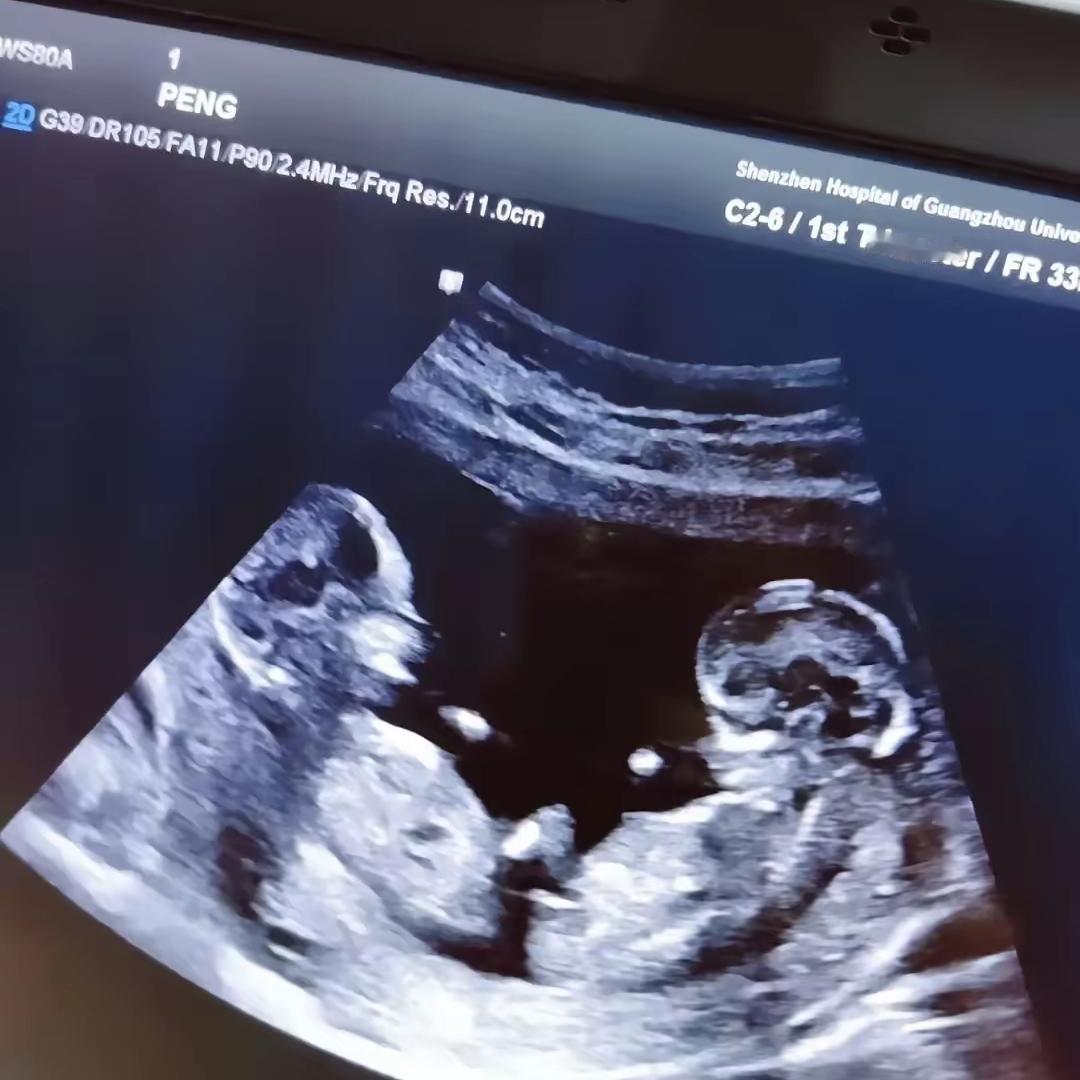

谁能想到啊,怀孕八个月居然还能被命运送一份“惊喜大礼”!湖北这位孕妈本来只是胎动太厉害去复查,结果B超一照,当场查出第二个心跳,连医生都看愣了。 之前三次产检都没发现,原来是两个宝宝贴得太紧,完美“隐身”了。这波操作真的太神奇,谁看了不感叹生命的奇妙。 本来准备好的是单胎待产包,现在紧急升级成双份,孕妈笑着笑着就开始愁,奶粉钱尿不湿直接翻倍,甜蜜的负担说来就来。 其实比起意外,平安才是最珍贵的礼物。晚到总比漏掉好,母子平安就是今年最好的消息。